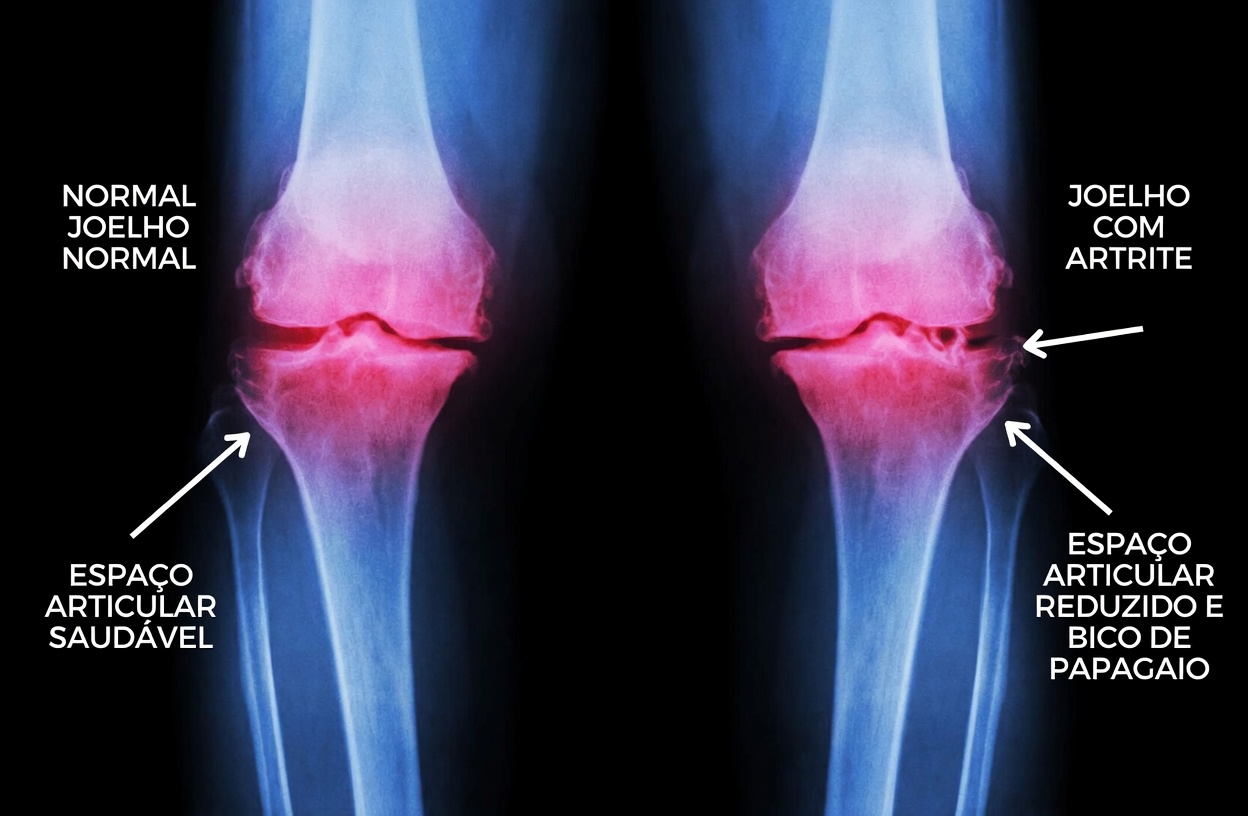

Quando a cartilagem se desgasta, o atrito entre os ossos pode aumentar, favorecendo inflamação e dor. Por isso, estratégias que ajudem a apoiar a integridade articular e a disponibilidade de componentes ligados ao colágeno ganham atenção.